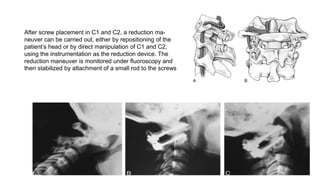

After screw placement in C1 and C2, a reduction ma-

neuver can be carried out, either by repositioning of the

patient’s head or by direct manipulation of C1 and C2,

using the instrumentation as the reduction device. The

reduction maneuver is monitored under fluoroscopy and

then stabilized by attachment of a small rod to the screws